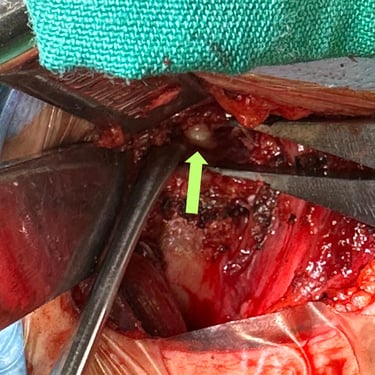

La hernia cervical es una causa frecuente de dolor en el cuello, hormigueo en los brazos y debilidad muscular. Cuando el tratamiento conservador no alivia los síntomas, la cirugía de discectomía cervical con artrodesis (ACDF) se convierte en una excelente alternativa. Este procedimiento consiste en retirar el disco dañado que comprime los nervios y reemplazarlo con un injerto o prótesis que estabiliza la columna. La ACDF ofrece alta tasa de éxito, mejorando el dolor, la fuerza y la calidad de vida. Gracias a técnicas modernas y una recuperación controlada, muchos pacientes vuelven rápidamente a sus actividades habituales.